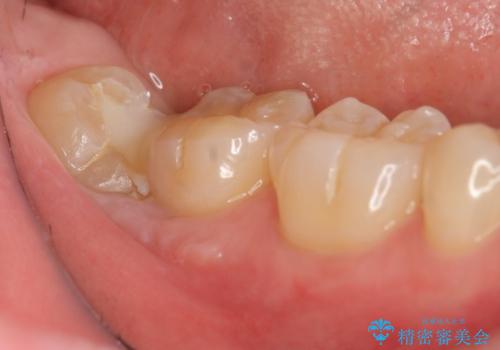

親知らずを起因とする虫歯治療

大きい虫歯 根管治療〜オールセラミッククラウン